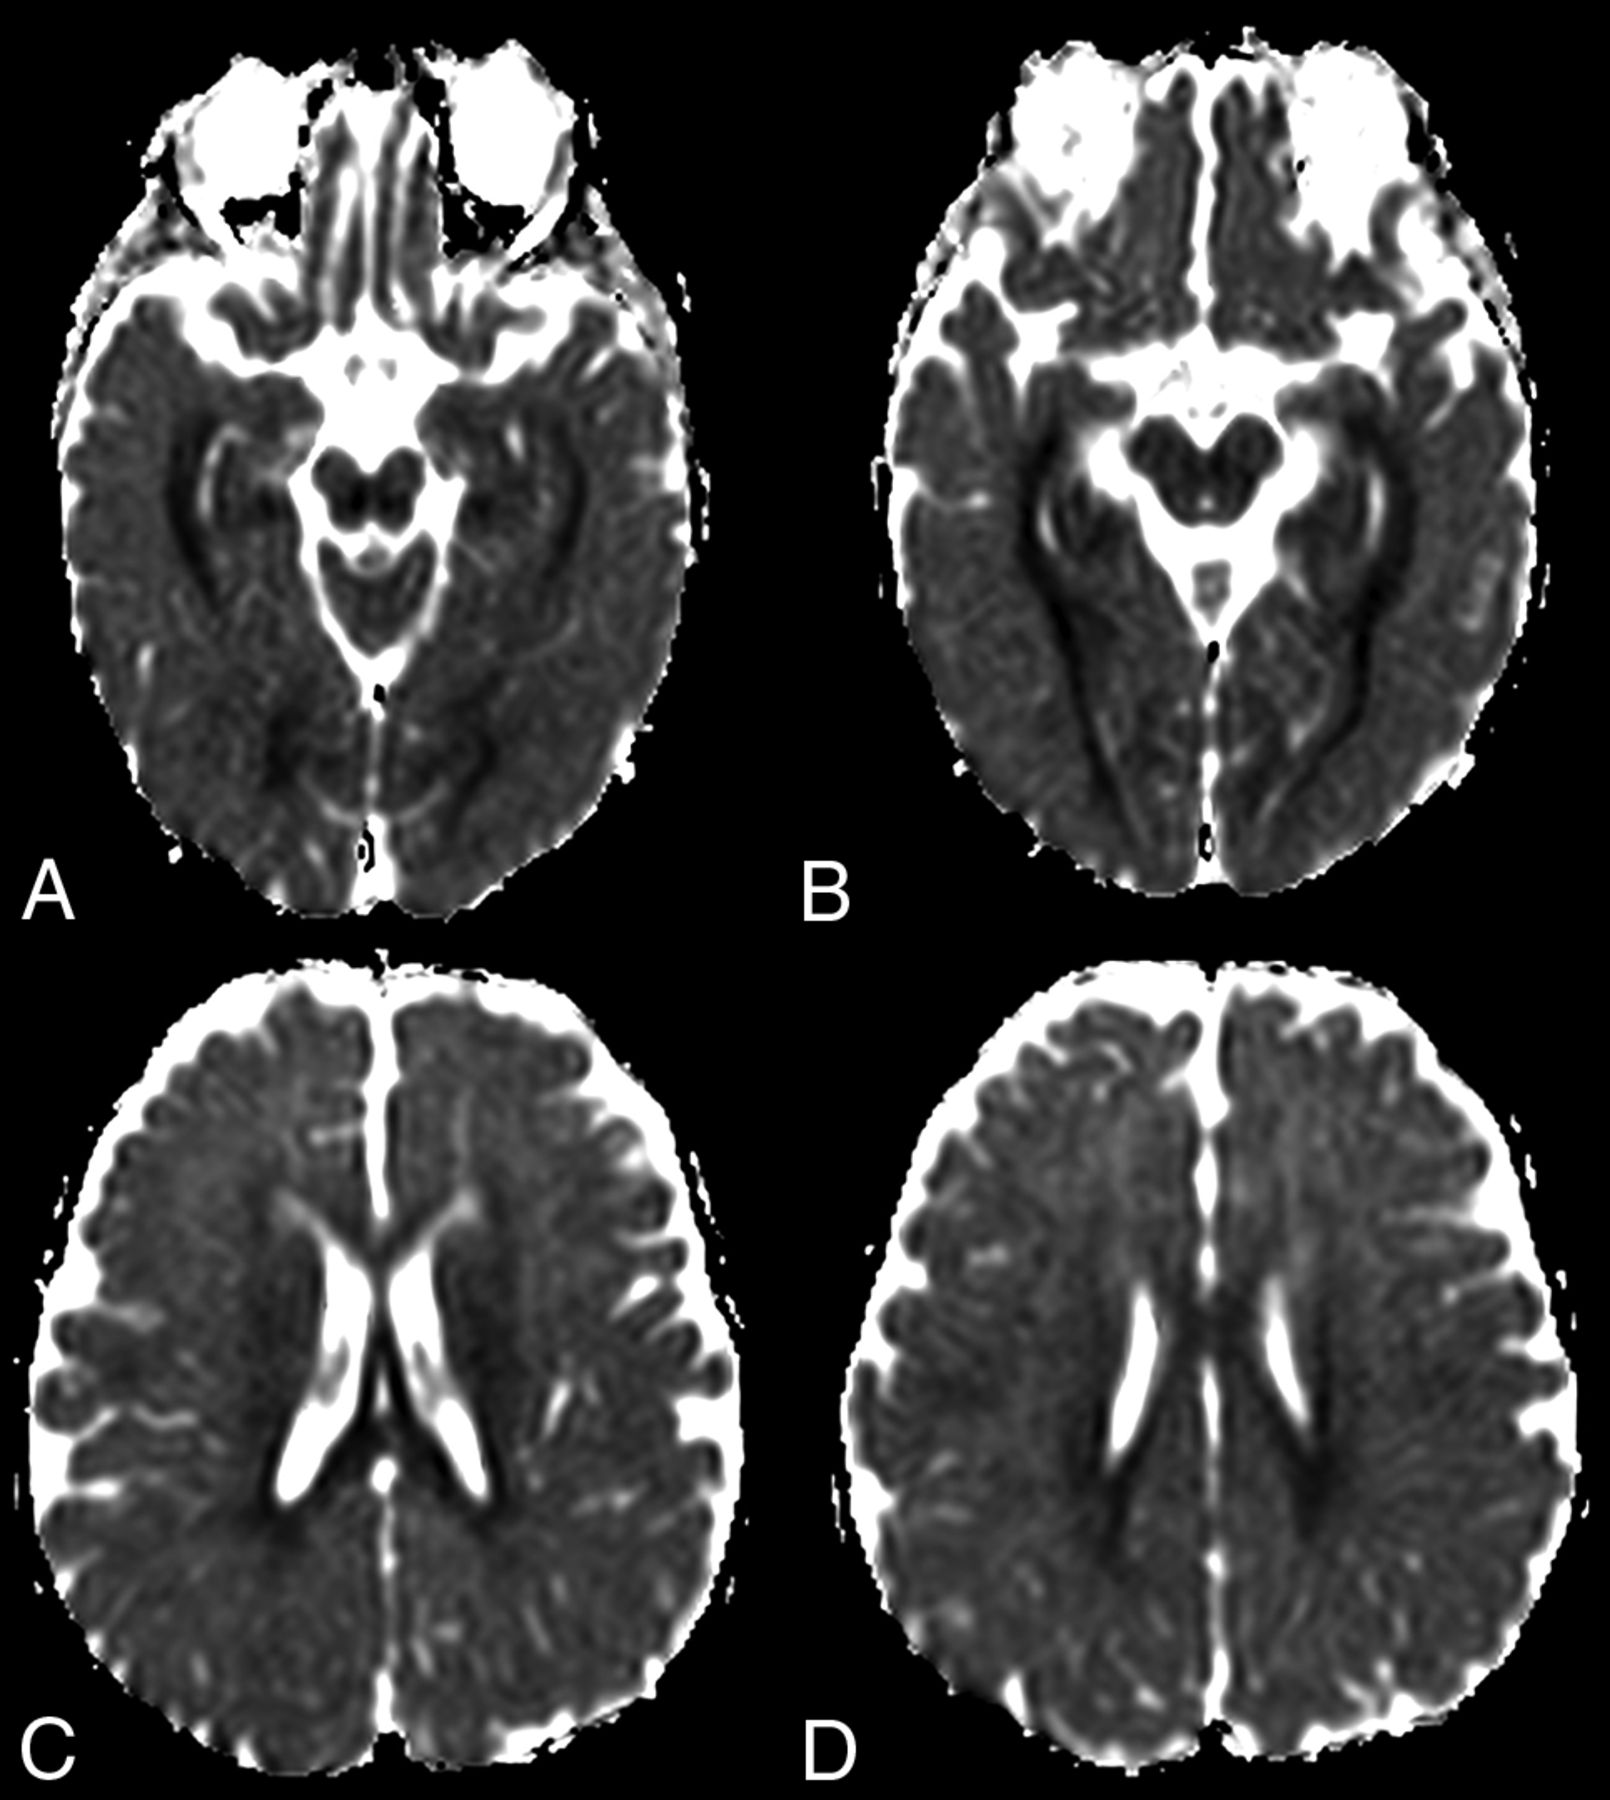

At diagnosis, brain MR imaging findings were abnormal in most patients (n = 12, 92%). The most common brain MR imaging findings were unilateral or bilateral perirolandic signal changes (n = 7, 54%) (Fig 1) and unilateral or bilateral thalamic signal changes (n = 10, 77%) (Fig 2). Perirolandic signal abnormalities were unilateral in most cases (n = 5, 71%) and were more frequently seen only affecting the precentral or both the pre- and postcentral gyri. Half of the thalamic changes were unilateral (n = 5, 50%). Simultaneous perirolandic and thalamic signal changes occurred in 6 patients (n = 6, 46%). An association of EPC (clinically/EEG) and perirolandic signal changes was present in 6 patients (n = 6, 75%), and an association of EPC (clinically/EEG) and thalamic signal changes, in 7 patients (n = 7, 87.5%). Two patients with EPC (clinically/EEG) did not present with perirolandic signal abnormalities. The findings positive for lesions overall were on the DWI of 10 patients (n = 10, 83%), on the T2WI of 9 patients (n = 9, 75%), and on FLAIR of 7 patients (n = 7, 58%). In 4 patients, DWI was the only sequence with abnormal findings. The occipital lobe was affected in the early brain MR imaging in 2 patients (n = 2, 15%). Signal changes in other brain regions were found in 5 patients (n = 5, 42%), involving multiple regions, namely the cerebral white matter, insula, putamen, caudate nucleus, fornix, cerebellar vermis, and also the frontal and occipital lobes. One patient did not present with either perirolandic or thalamic changes but instead presented with a diffuse pattern similar to that of leukoencephalopathy, with restricted diffusion in the white matter and white matter tracts (Fig 3). Three patients had an abnormally high lactate peak on MR spectroscopy. None of our patients had ASL or other perfusion-weighted imaging at the time of diagnosis. T1 and T2* imaging and SWI had negative findings at the time of diagnosis.

MR imaging thalamic signal changes in 3 different patients with POLG-related disorders (A, A 9-month-old female), (B, A 3-year-old female), and (C, A 3-year-old male). Thalamic signal changes were also variable with varying degrees of conspicuity. A, DWI. Signal changes were subtle and focal with restricted diffusion in the right thalamus (open arrow). B, FLAIR. Signal changes involved both thalami, more conspicuous on the left side (open arrows). C, T2WI. Signal changes were bilateral and symmetric involving both thalami (open arrows).

Thalamic signal changes were also frequent at the time of diagnosis and on follow-up imaging. Unilateral or bilateral thalamic involvement was identified in most patients during the onset of their disease. In our cohort, there was no new thalamic involvement at follow-up. On follow-up imaging, thalamic changes had different outcomes: complete resolution, progression from unilateral to bilateral involvement, progression accompanied by volume loss, and fluctuation with periods of an almost-complete resolution and frank progression. Thalamic signal changes were variably detected on DWI, T2WI, FLAIR, or ASL.